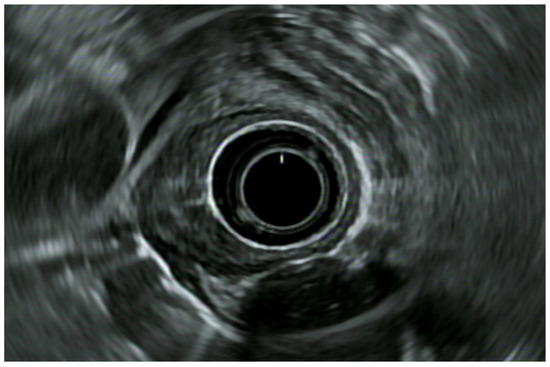

8.3. Rectal Subepithelial Lesions

8.4. Inflammatory Bowel Disease (IBD) and Anal Incontinence

- Chen, H.-T.; Xu, G.-Q.; Teng, X.-D.; Chen, Y.-P.; Chen, L.-H.; Li, Y.-M. Diagnostic accuracy of endoscopic ultrasonography for rectal neuroendocrine neoplasms. World J. Gastroenterol. 2014, 20, 10470–10477. [Google Scholar] [CrossRef] [PubMed]

- Pagano, N.; Ricci, C.; Brighi, N.; Ingaldi, C.; Pugliese, F.; Santini, D.; Campana, D.; Mosconi, C.; Ambrosini, V.; Casadei, R. Incidental diagnosis of very small rectal neuroendocrine neoplasms: When should endoscopic submucosal dissection be performed? A single ENETS centre experience. Endocrine 2019, 65, 207–212. [Google Scholar] [CrossRef] [PubMed]